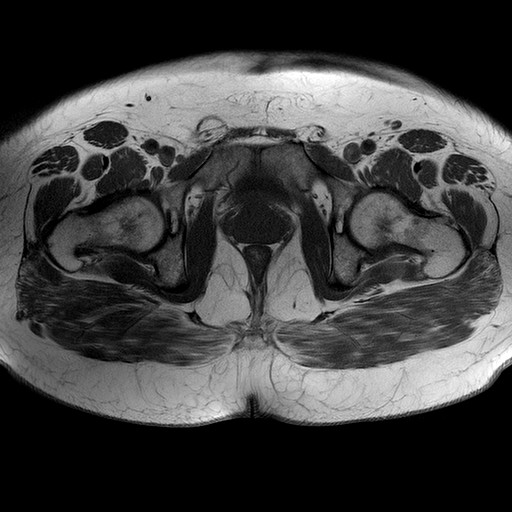

Esami: RMN BACINO

T1W_TSE

Evidenti e simmetriche alterazioni osteofitosiche in regione coxo femorale con riduzione delle rime articolari. Degenerazione completa del cercine glenoideo. Non attuali segni di versamento articolare. Non segni di edema osseo che escludono attuale algodistrofia od osteonecrosi. Lieve e simmetrica riduzione del trofismo della muscolatura glutea.